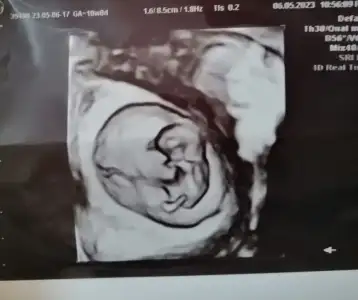

Bugün tam 10 haftalık karından plasentayı da çizdim doktor söyledi orası olduğunu tahminini bekliyorumBurada kaç haftalık? Parlak alan solda gibi eğer karından ultrason ise erkek diye anlıyorum :)

10 haftalık karından bi tahmin alabilir miyiz lütfeeeeenMaşallahsanırım 9 haftalık bana kız gibi geldi ama tamamen öylesine his